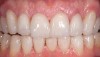

Figure 5  Image of minimal preparations prior to application of the bonded porcelain.

Figure 5

Figure 6  Two-year postoperative image of very conservative Category 1 bonded porcelain restorations.

Figure 6